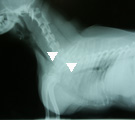

受診時。気管虚脱に対し気管内挿管の緊急処置が施されていた。 第1病日胸部X線写真。気管チューブを抜くと胸郭前口部で気管陰影消失(三角マーク間)。 引き続き、気管切開してシリコン製Tチューブを設置し気道確保した(マークはチューブ端を示す)。 第79病日、自己拡張型金属ステントに入れ替え、気管開存性と気道違和感が著明に改善した。

経過:町田夜間動物病院からの引継ぎで生命危機に関わる重度な気管虚脱であることが予想できたので、即座に慎重な治療計画を立てる必要性があった。気管内チューブ下では、違和感はあったが、room air吸入下でSpo2は97%を示し、肺機能は保てていた。Tチューブによる気道確保まで行う予定で万全の準備を整え、気管チューブを一度抜いた。予期していたとおり、ただちに呼吸困難とチアノーゼが生じた。すばやくビデオ透視と胸部X線撮影を実施し、ただちに麻酔導入し再挿管した。まず、将来的に自己拡張型金属ステント(Expandable metaric stent, EMS)を設置する可能性を考慮し、食道内にsizingカテーテルを挿入し気道内圧を20cmH2Oに保ち気管を拡張させX線撮影を行った。その後、気管支鏡検査にて、気管虚脱の範囲を同定し、また気管分岐部以降の虚脱がないことを確認した。Tチューブ設置のための気切部位は、X線所見と気管支鏡所見で同定した気管虚脱範囲の中点にあたる第5頚椎の部位とした。外径は輪状軟骨部の気管径の90%程度になるものを選び、8mmに決定した。気切孔から中枢側に大部分摺りこませ、口腔側へはガイドワイヤーを用い牽引して確実に引き寄せTチューブを設置した。設置後翌日より呼吸状態は改善し、食欲や一般状態もただちに回復した。術後管理は、1日2回のネブライゼーション(抗生剤、エピネフリン、生理食塩水、ステロイド)、Tチューブの気切部の栓を抜いて貯留痰の除去・吸引、1日2回の抗生剤の注射で行ったが、経過良好のため術後8日目に退院とした。自宅管理は、喀痰培養の結果に応じて抗生剤の処方を変えていったが、やはり入院時同様に1日2回のネブライゼーション、痰の除去、抗生剤の内服を継続した。Tチューブで管理中に、アメリカのEMSメーカーに気管sizingを含めた胸部X線写真の評価を依頼し、外径12mmX長さ52mmのステントを使用するよう指示された。ステント入手まで約1ヶ月程度を要した。しかしその間、軽度の咳がみられたがTチューブにて気管虚脱を十分よくコントロールできた。結局、オーナーと当院の都合が合い、犬の状態のよいときに(第79病日)、EMSへの交換を安全に無理なく行うことができた。EMS設置後、さらに状態は改善し、術翌日に非常に強く大きな声で吠えるになり、Tチューブ設置時より俊敏に動きまわるようになり、術後4日目に退院となった。第92病日、咳は消失した。